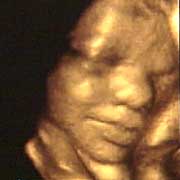

圖文:胎兒子宮內(nèi)表情豐富 專(zhuān)家稱(chēng)提供研究新依據(jù)

中新網(wǎng)9月13日電 英國(guó)天空新聞報(bào)道,英國(guó)科學(xué)家圖亞特·坎貝爾最近利用先進(jìn)的掃描技術(shù)清晰地拍下了孕婦子宮中胎兒的表情,透過(guò)他拍攝的照片,人們可以清楚的看到一個(gè)尚未降臨世間的小生命喜、怒、哀、樂(lè)的表情。

斯圖亞特.坎貝爾是倫敦著名的產(chǎn)科教授,他利用超聲掃描技術(shù)拍攝到了胎兒在子宮中打呵欠、眨眼、吮手指、哭泣甚至微笑的畫(huà)面,這些都為胎兒行為的研究提供了新的依據(jù),專(zhuān)家認(rèn)為,這一突破將推動(dòng)?jì)雰航】悼茖W(xué)的發(fā)展,包括對(duì)唐氏綜合癥等嬰幼兒疾病的診治將起到極大的推動(dòng)作用。

此前,醫(yī)學(xué)界一直認(rèn)為,嬰兒要到降生后才可以做出喜、怒、哀、樂(lè)的表情,要通過(guò)模仿母親才可以學(xué)會(huì)微笑。

坎貝爾教授說(shuō):“有個(gè)這種技術(shù),現(xiàn)在許多問(wèn)題都可以進(jìn)行研究了。比如說(shuō),患有唐氏綜合癥的嬰兒和正常嬰兒的活動(dòng)方式是否一樣?胎兒是否因?yàn)楦吲d才笑?胎兒哭是否是因?yàn)樵谧訉m中受到打擾?既然我們都認(rèn)為子宮內(nèi)是一片黑暗,那胎兒為什么會(huì)眨眼呢?”(章田)